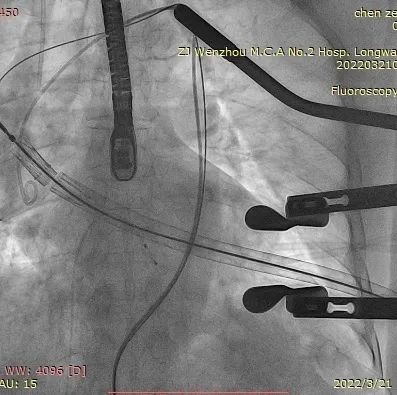

瓣膜释放泥鳅导丝和单弯管过弓

加硬导丝建立轨道

介入器过瓣环平面

释放定位件

瓣膜入座

瓣膜自膨

松开锁丝,撤出输送器

DSA和TEE显示无瓣周漏,瓣膜位置、形态良好